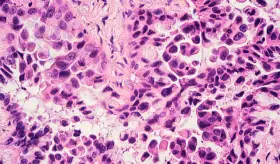

Gracias a la investigación, han surgido nuevas terapias como anticuerpos biespecíficos, tratamientos dirigidos y combinaciones con quimioterapia que están mejorando la respuesta y la progresión de estos pacientes.

Incorporaciones de tecnologías han permitido realizar diagnósticos y estadificación en un solo procedimiento, optimizando tiempos, reduciendo riesgos y mejorando las decisiones terapéuticas para los pacientes.